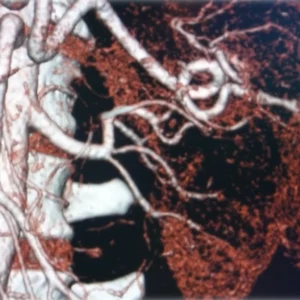

Renal arteriogram

A renal arteriogram is a special type of X-ray picture that helps doctors see the blood vessels in your kidneys.